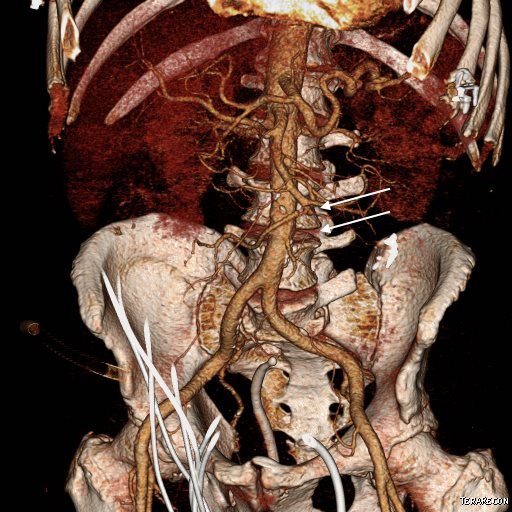

The patient is a middle aged man with risk factors of NIDDM and prior history of DVT who developed severe mid-abdominal pain at 5pm. He came to the ED at around 11pm and had a general surgery consultation who ordered a CT Angiogram showing SMA occlusion (pictured below).

Heparin was started, and at 11:30, vascular surgery was consulted. The patient had a soft, doughy texture to his abdomen, but great pain with palpation -classic pain out of proportion to the exam. Determining the patient to have acute mesenteric ischemia from a thromboembolism, I took the patient to our hybrid angiographic OR suite with the plan for arteriography, possible open thrombectomy, and exploratory laparotomy.

Arteriography from femoral access showed an occlusion of the SMA beyond the middle colic artery, a typical pattern for an embolism that occurs when embolism lodges distally and propogates proximally (image below).